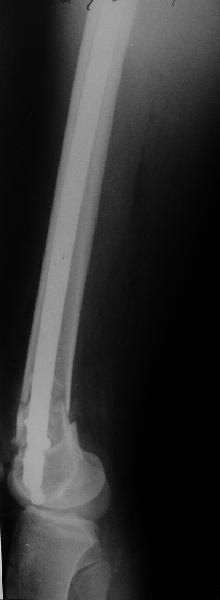

I> Насчет снимка Вами представленного - смотрится оч красиво, еще бы на

I> функцию узнать...

В приложении функциональные снимки в 3 мес. и в 1 год.